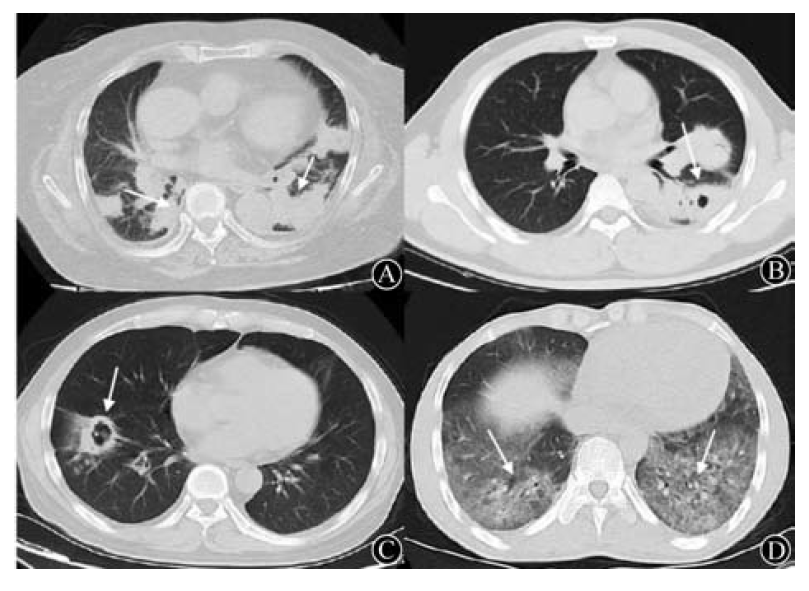

肺隐球菌病影像学表现多种多样,主要取决于宿主的免疫状态。

免疫功能正常患者肺部病灶大多数较局限,以单发/多发的周围型结节团块及局限的肺炎样病灶最为多见,结节团块型边缘可有毛刺和分叶改变,病灶大多分布于下肺外周呈宽基底状,紧贴胸膜,以右下肺较常见。

免疫抑制患者常见表现包括胸膜下区为著的单发或多发结节、局灶性实变区,边缘不清的斑片状实变或伴有空气支气管征的边缘清楚的实变,形成空洞和晕征;少见表现有肺门和纵隔淋巴结肿大,弥漫性粟粒状影,急性间质性肺炎,胸腔积液,网格状浸润,磨玻璃样渗出影。

图4 肺隐球菌病的影像学表现:A,单发的周围型的结节团块;B,多发的周围型结节团块;C,局限的肺炎样病灶;D,多发团块